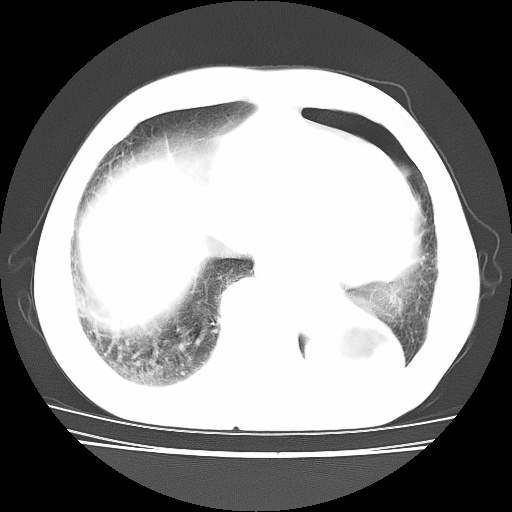

男,71岁,咳嗽,气喘10年,再发并咯血.胸片见气胸

考虑  左肺中心型肺癌伴阻塞性肺炎,肺不张,纵膈淋巴结肿大。慢支炎,肺气肿,左侧气胸肺压缩5%

左侧中央型肺癌伴纵膈淋巴结转移。

左肺中心型肺癌伴阻塞性肺炎,肺不张,纵膈淋巴结肿大

1)考虑左肺中心型肺癌伴阻塞性肺炎、左肺下叶肺不张、左侧肺气肿,纵膈淋巴结转移。2)左侧气胸(肺组织压缩约5%)。

左肺中心型肺癌伴阻塞性肺不张、肺气肿 。

1)考虑左肺中心型肺癌伴阻塞性肺炎、左肺下叶肺不张、左侧肺气肿,纵膈淋巴结转移。2)左侧气胸。